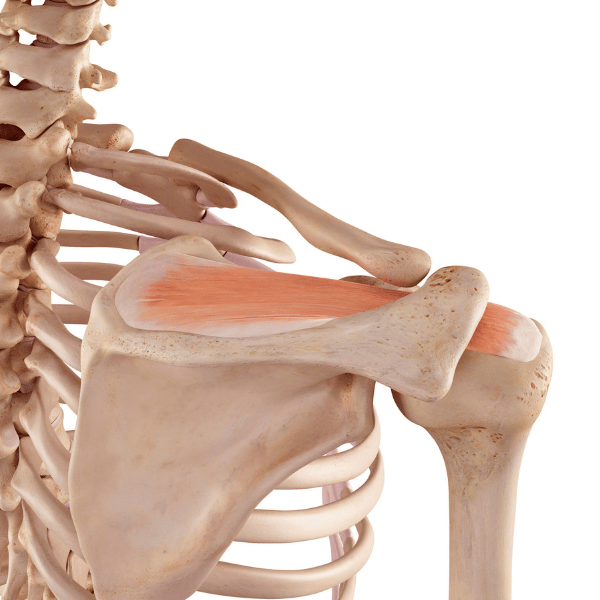

Še en pomemben dejavnik je ustrezna stabilnost v trupu – s tem ne mislimo na prekomerno stiskanje mišic ali pretiravanje s trebušnjaki, temveč ustrezna moč in medsebojna koordinacija globokih stabilizatorjev, med katere spadajo globoka trebušna mišica, prepona oz. diafragma ter multifidi (drobne mišice med vretenci). Njihova ustrezna aktivnost zmanjša nepotrebne sile, ki jim je hrbtenica dnevno izpostavljena.

Človeško telo je zelo kompleksno in deli so medsebojno povezani, zato moramo biti pozorni tudi na dele, ki s hrbtenico niso neposredno povezani. Še posebej je pomembno področje bokov oz. kolčnega sklepa, saj sta ustrezna moč in gibljivost bokov odlična preventiva za preobremenjevanje hrbtenice, še posebej pri dvigovanjih bremen, priklanjanju, seganju – pri tovrstnih gibih se manko moči, gibljivosti ali kontrole gibanja sile hitro prenesejo na hrbtenico. Vložek časa v učenje pravilnega priklanjanja in dvigovanja bremen se izplača, saj bo hrbtenica veliko manj obremenjena, če se naučimo izkoristiti mišične skupine, ki imajo za tovrstne naloge veliko večjo kapaciteto kot pa drobne strukture ob vretencih.

Skupina vaj s pomembno funkcijo so vaje za globoke stabilizatorje. V primeru vratne spondiloze so to globoke upogibalke vratu, z njihovo krepitvijo razbremenimo mišice na površini, saj se zaradi njihove prekomerne aktivnosti poveča kompresija na vratna vretenca. V primeru ledvene spondiloze pa so to globoki stabilizatorji trupa, ki pomagajo pri stabilizaciji in podpori hrbtenice.

Čeprav je moč stabilizatorjev pomembna, se življenje ne dogaja na tleh na blazini, ampak je precej bolj dinamično, zato ne smemo zanemariti krepitve večjih mišičnih skupin, ki opravljajo raznovrstne funkcionalne gibe. Mišice nog, kolčnega in ramenskega predela pomagajo prevzemati ogromno sil, ki jih je med gibanjem deležno naše telo. Brez ustrezne moči naštetih mišic je naša hrbtenica primorana absorbirati večje sile kot če se sile ustrezno razporedijo po telesu.